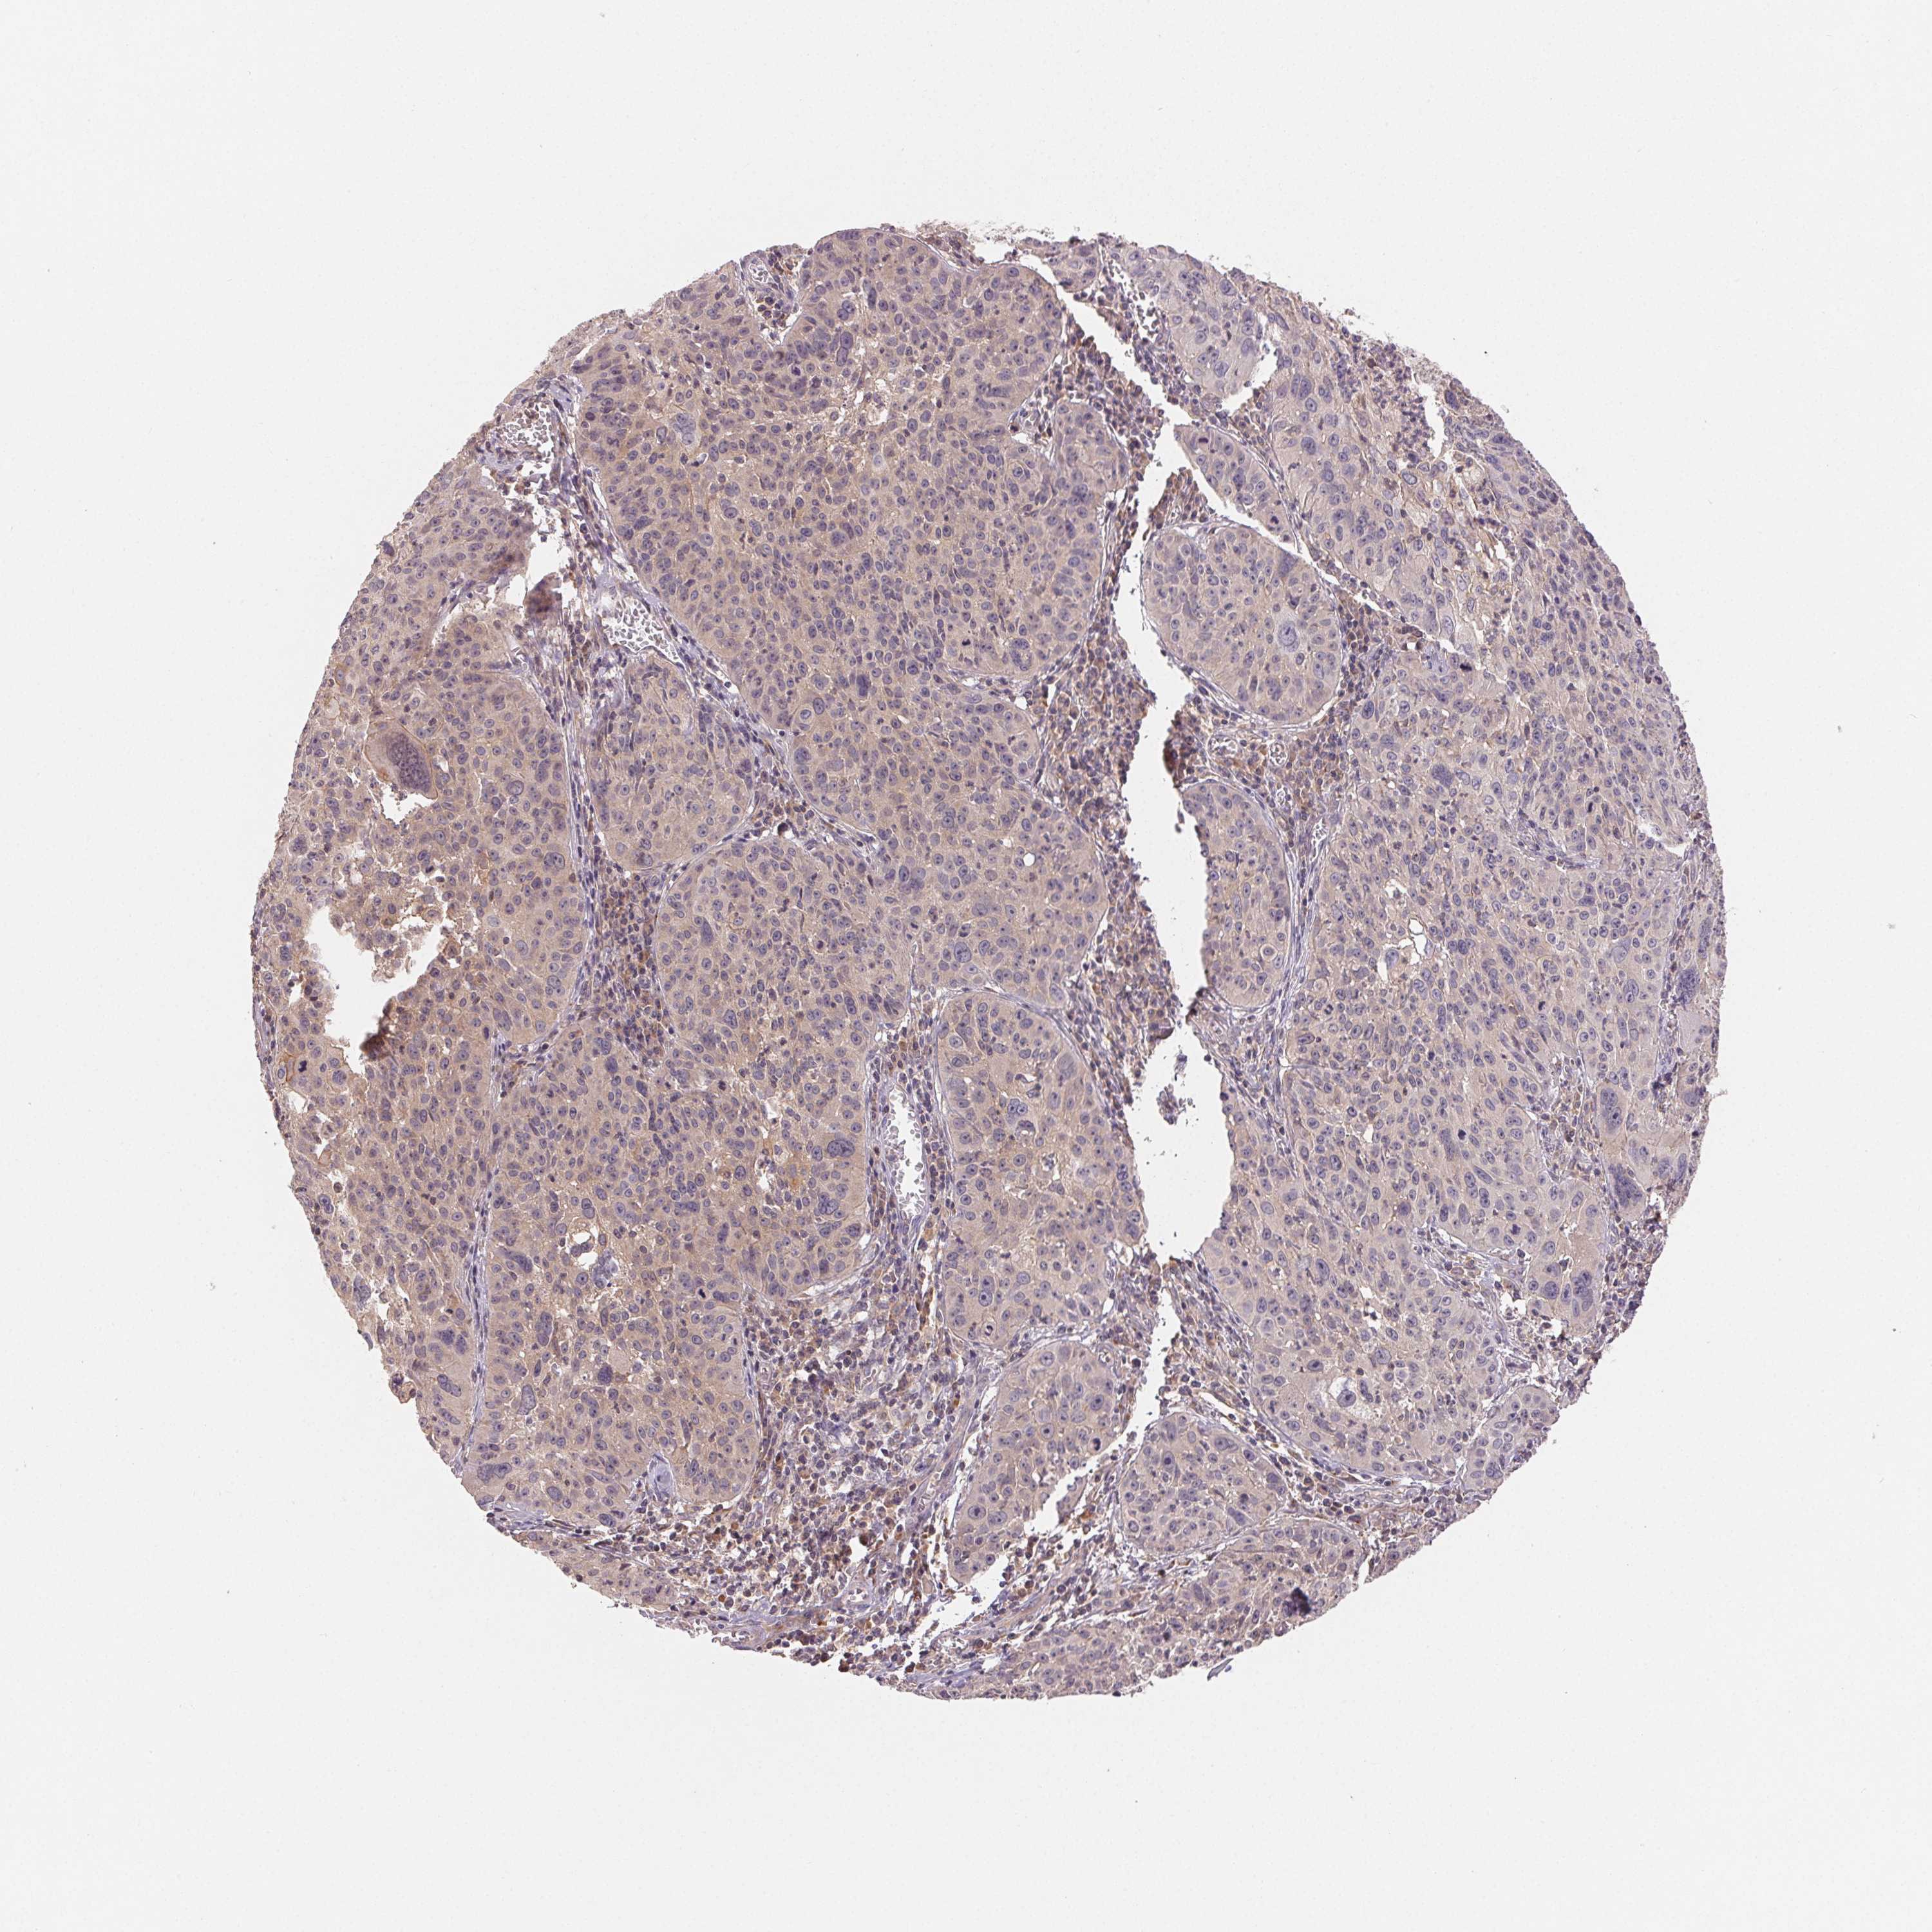

CERVICAL CANCER - Protein expressioni

A mouse-over function shows sample information and annotation data. Click on an image to view it in a full screen mode. Samples can be filtered based on level of antibody staining by selecting one or several of the following categories: high, medium, low and not detected. The assay and annotation is described here.

Note that samples used for immunohistochemistry by the Human Protein Atlas do not correspond to samples in the TCGA dataset.

Antibody stainingi

Antibody staining in the annotated cell types in the current human tissue is reported as not detected, low, medium, or high, based on conventional immunohistochemistry profiling in selected tissues. This score is based on the combination of the staining intensity and fraction of stained cells.

Each image is clickable and will lead to virtual microscopy that enables deeper exploration of all samples and also displays staining intensity scores, fraction scores and subcellular localization as well as patient and tissue information for each sample.

Antibody HPA063708

Antibody HPA064435

Antibody CAB010297

Squamous cell carcinoma, NOS